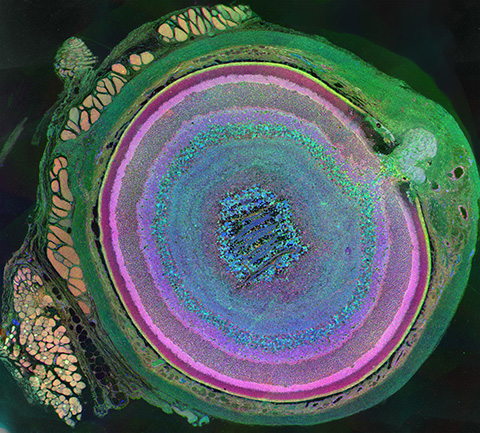

Most eye exams include fundus photography, a snapshot of the retina, optic nerve and vessels. These images form the baseline of modern vision care, and with AI, they become even more powerful. Algorithms can now analyze the photos to provide earlier, clearer answers, often with quicker, more comfortable scans.

Fluids and tissues inside the eye distort light, adding blur to optical images. To correct this, researchers use adaptive optics, or AO, a technology originally developed in the 1950s to sharpen telescope views of distant stars.

An AO-assisted retinal imager uses a deformable mirror to cancel distortions, producing corrected images captured by a camera. The addition of AI reduces AO scan times from hours to minutes while preserving cellular detail.

Tam and Joanne Li, a biomedical engineer at NEI’s Clinical and Translational Imaging Section, built a system that recovers features of the retinal pigment epithelium, or RPE, from standard clinical scans. RPE cells nourish photoreceptors, which enable vision and are disrupted in many eye diseases. Seeing cell-level changes early can change the course of care.

The NEI team also developed P-GAN, an AI model that sharpens AO optical coherence tomography, which images 3D retinal structures at the cellular level. Instead of collecting hundreds of 3D images to reduce noise, P-GAN cleans them computationally, even improving results from low-cost cameras.